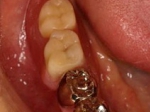

抜歯を行う。折れていた位置がかなり深い位置であるのがわかる。

歯根も抜歯

抜歯した穴をよく掃除(掻爬)後すぐにインプラントを埋入